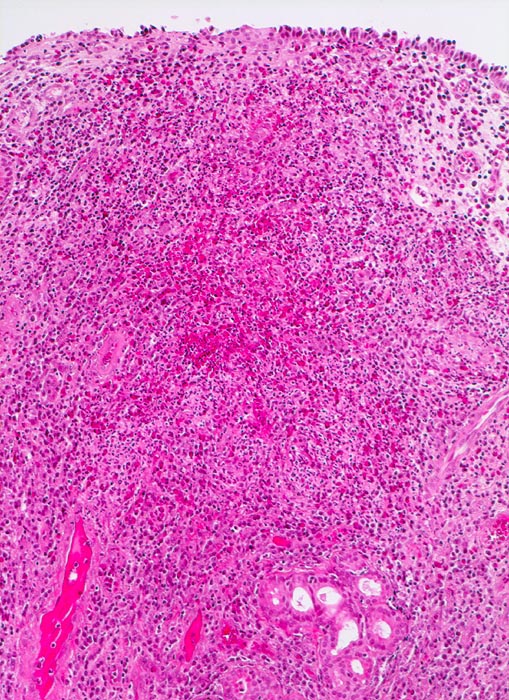

• Polypoides Gewebsfragment bedeckt von mehrreihigem Flimmerepithel.

• Herdförmige Schleimhauterosionen.

• Ödematöses Stroma mit gemischtem Entzündungsinfiltrat: Lymphozyten, Plasmazellen, Histiozyten und zahlreiche eosinophile Granulozyten.

• Im Zentrum des Polypen Drüsenläppchen und zahlreiche Blutgefässe.